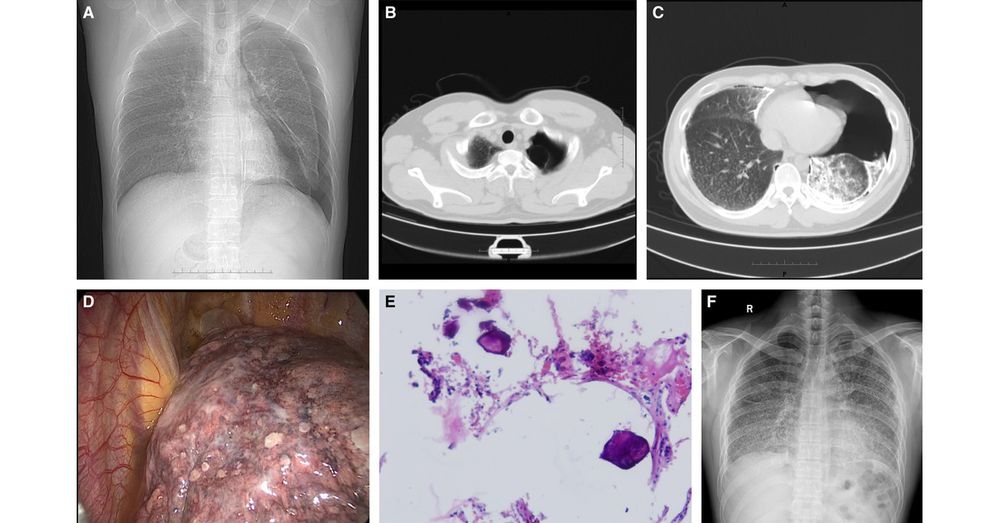

Spontaneous Pneumothorax as First Presentation of Pulmonary Alveolar Microlithiasis